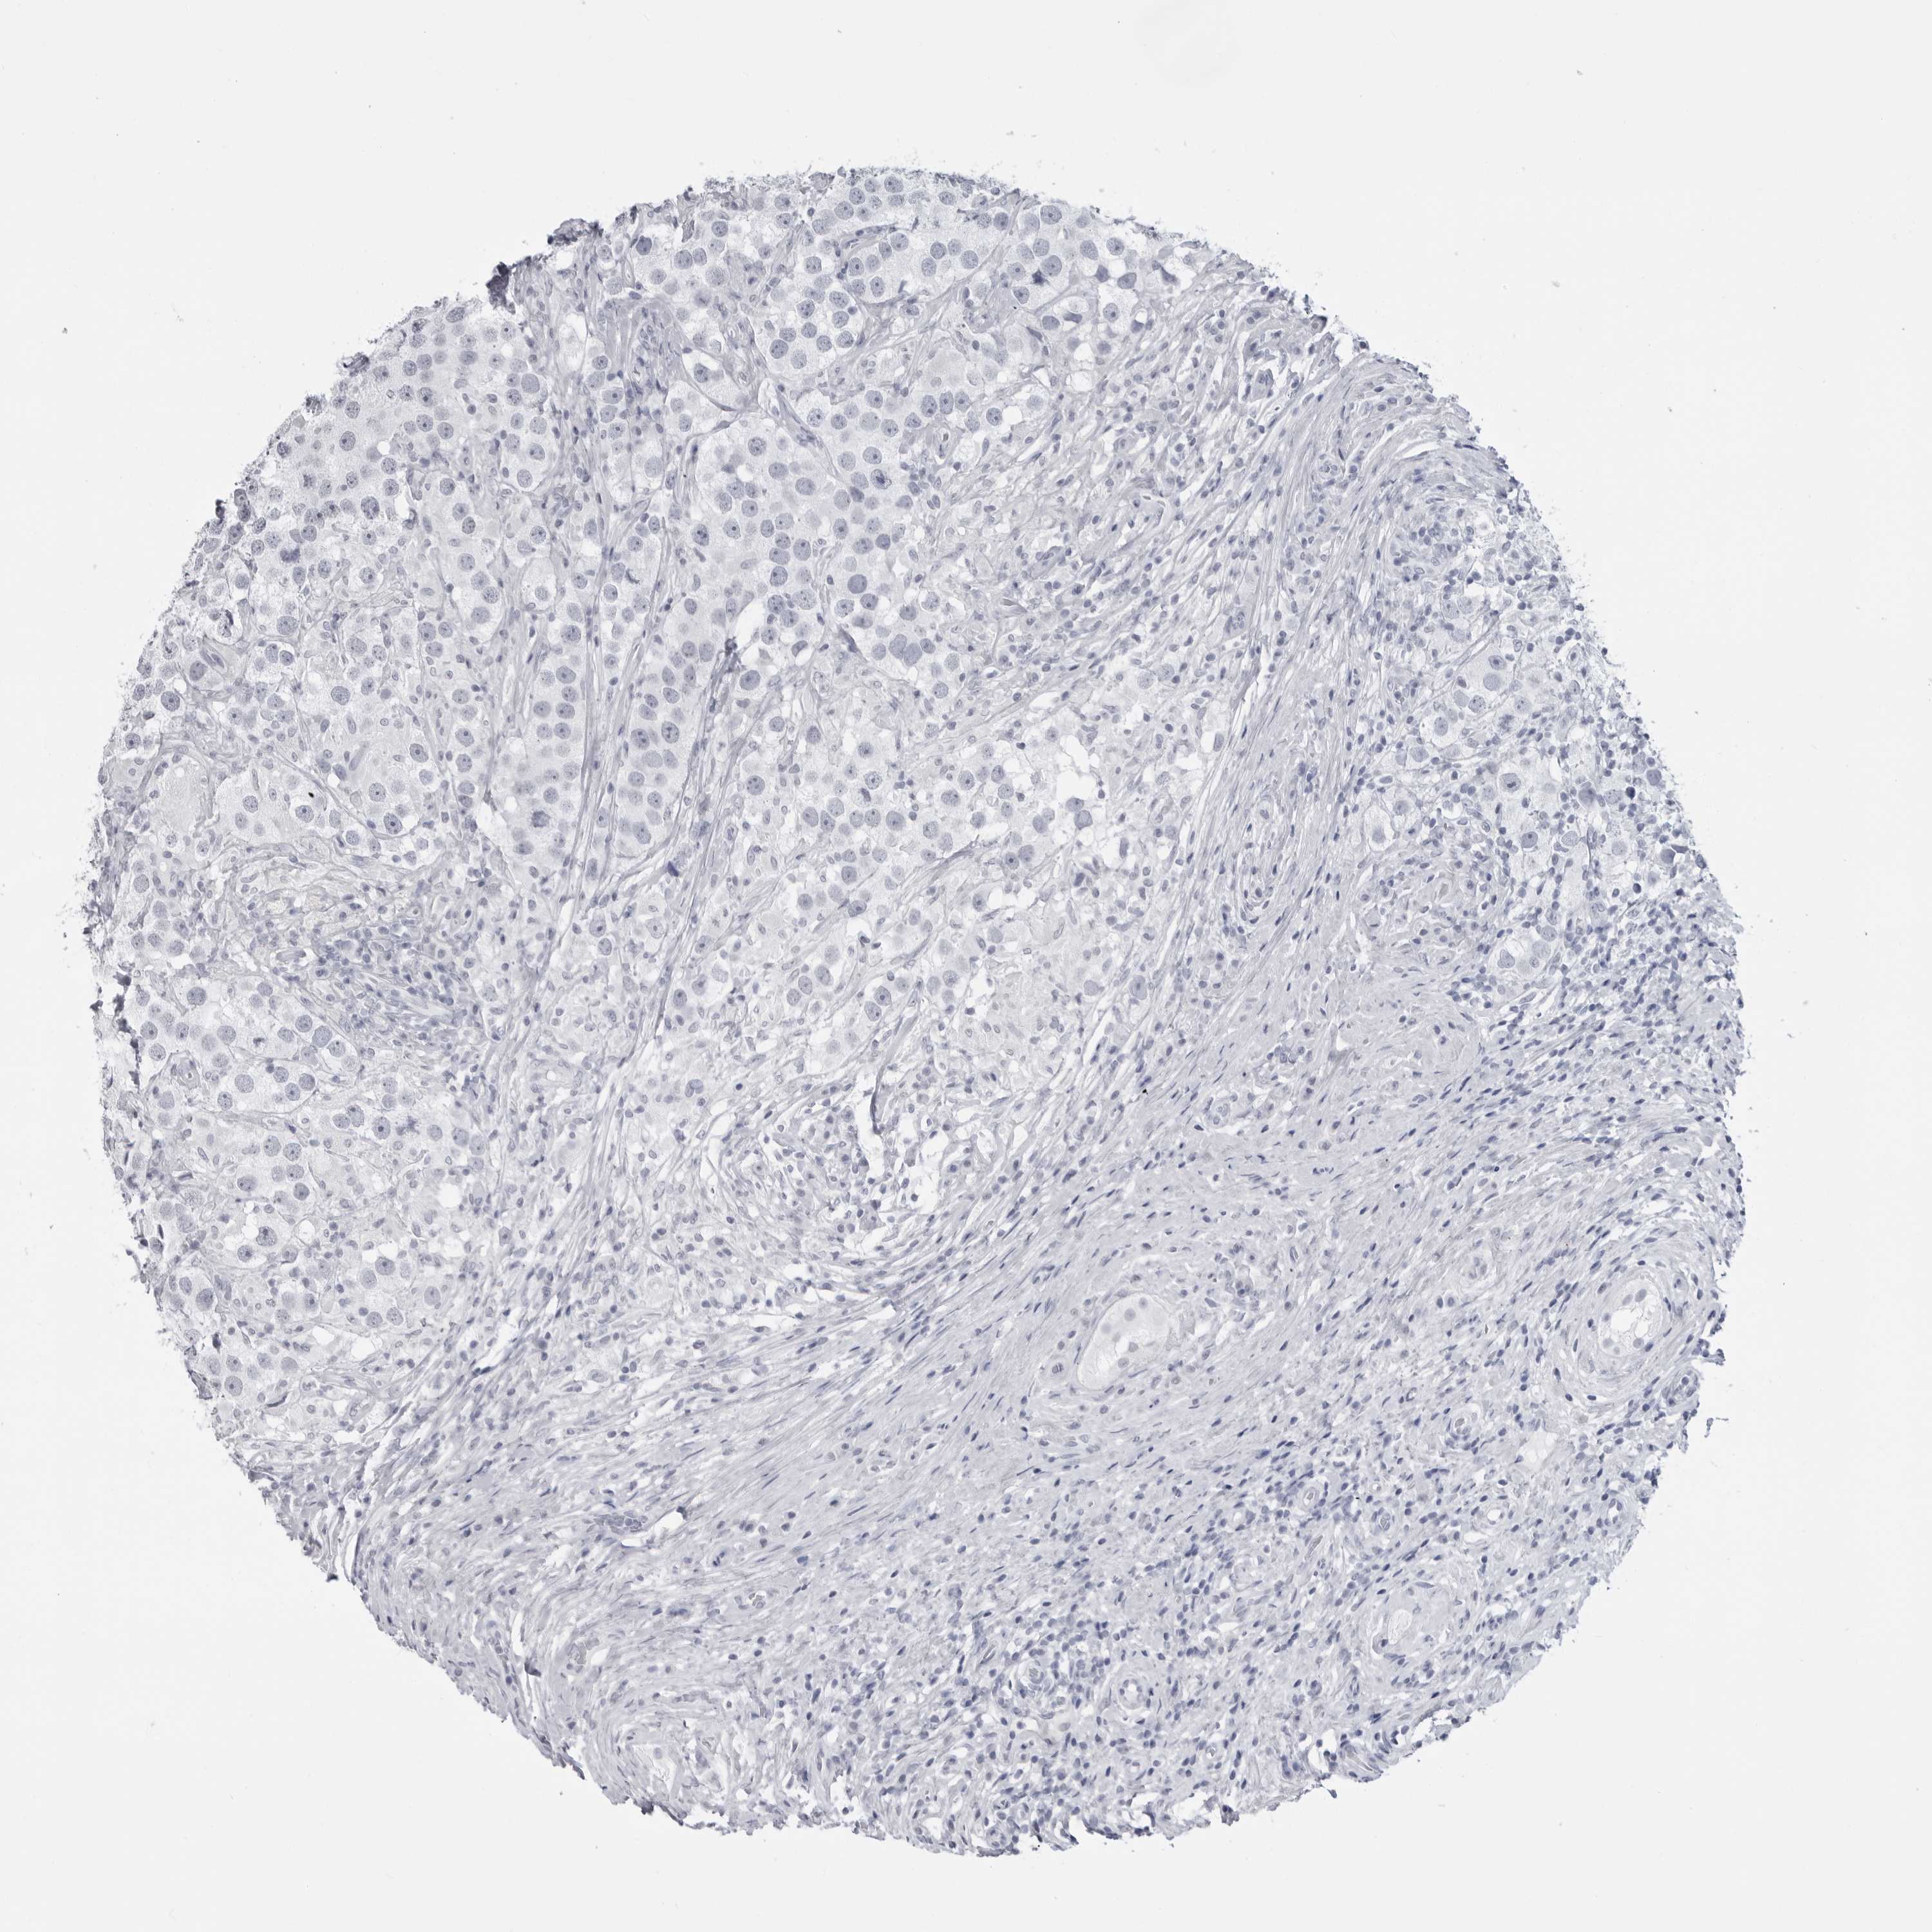

TESTIS CANCER - Protein expressioni

A mouse-over function shows sample information and annotation data. Click on an image to view it in a full screen mode. Samples can be filtered based on level of antibody staining by selecting one or several of the following categories: high, medium, low and not detected. The assay and annotation is described here.

Note that samples used for immunohistochemistry by the Human Protein Atlas do not correspond to samples in the TCGA dataset.

Antibody stainingi

Antibody staining in the annotated cell types in the current human tissue is reported as not detected, low, medium, or high, based on conventional immunohistochemistry profiling in selected tissues. This score is based on the combination of the staining intensity and fraction of stained cells.

Each image is clickable and will lead to virtual microscopy that enables deeper exploration of all samples and also displays staining intensity scores, fraction scores and subcellular localization as well as patient and tissue information for each sample.

Antibody HPA046875

Antibody CAB026358

Seminoma, NOS

Carcinoma, Embryonal, NOS